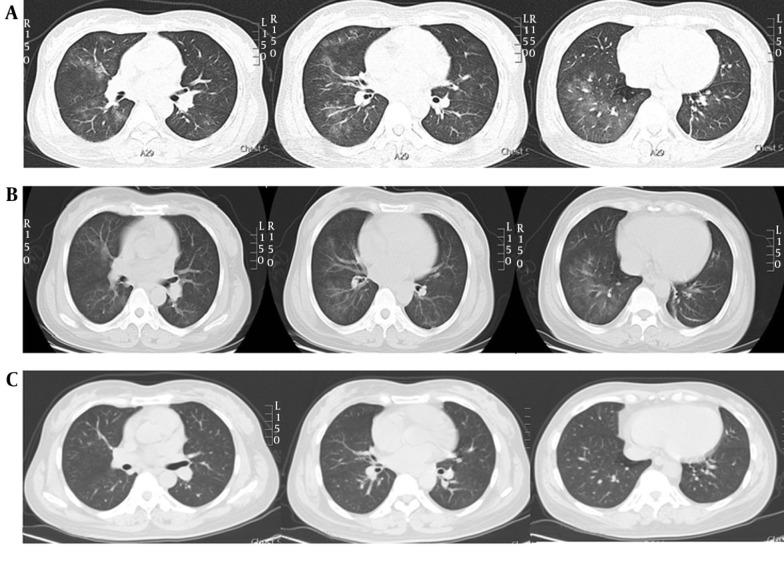

A 43-year-old woman with Graves' disease developed pulmonary vasculitis and diffuse alveolar hemorrhage (DAH) associated with ANCA against myeloperoxidase and proteinase-3 that was confirmed by computed tomography (CT) and bronchoscopy and treated with PTU. The symptoms and signs of alveolar hemorrhage were rapidly resolved after PTU withdrawal and treatment with corticosteroids. After 6 months of follow-up, the patient maintained complete ANCA-negative clinical remission status, as confirmed by normal CT and bronchoscopy findings. To our knowledge, this is the first documented case of bronchoscopic comparison of PTU-induced DAH before and after steroid treatment.

一名43岁的格雷夫斯病女性患者出现了与抗髓过氧化物酶和蛋白酶-3的ANCA相关的肺血管炎和弥漫性肺泡出血(DAH),通过计算机断层扫描(CT)和支气管镜检查得以确诊,患者此前接受PTU治疗。停用PTU并给予糖皮质激素治疗后,肺泡出血的症状和体征迅速缓解。经过6个月的随访,患者维持完全的ANCA阴性临床缓解状态,CT和支气管镜检查结果均正常证实了这一点。据我们所知,这是首例记录了类固醇治疗前后PTU诱导的DAH的支气管镜比较的病例。